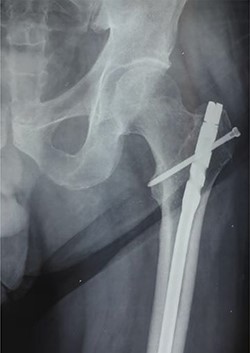

Anteroposterior radiograph showing the tip of the intramedullary nail right at the level of the greater trochanter.